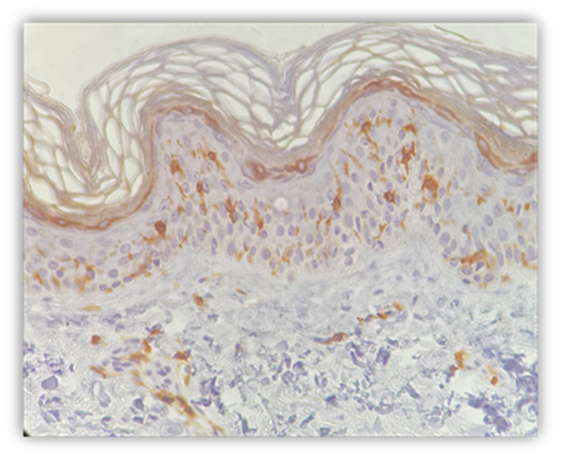

Figura 1. Inmunohistoquimica: medición de células de Langerhans antes del uso de PL.